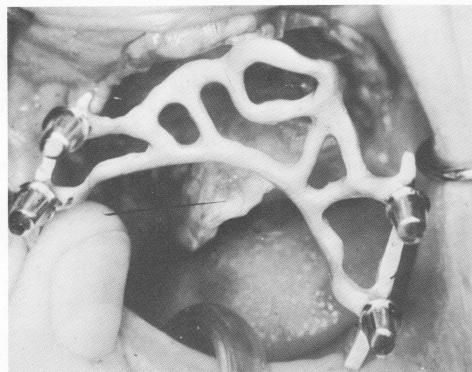

Fig. 11-179. The completed cobalt-chrome one-piece casting of the palatal horseshoe type blade.

1 Palatal horseshoe type blade insertion in maxilla